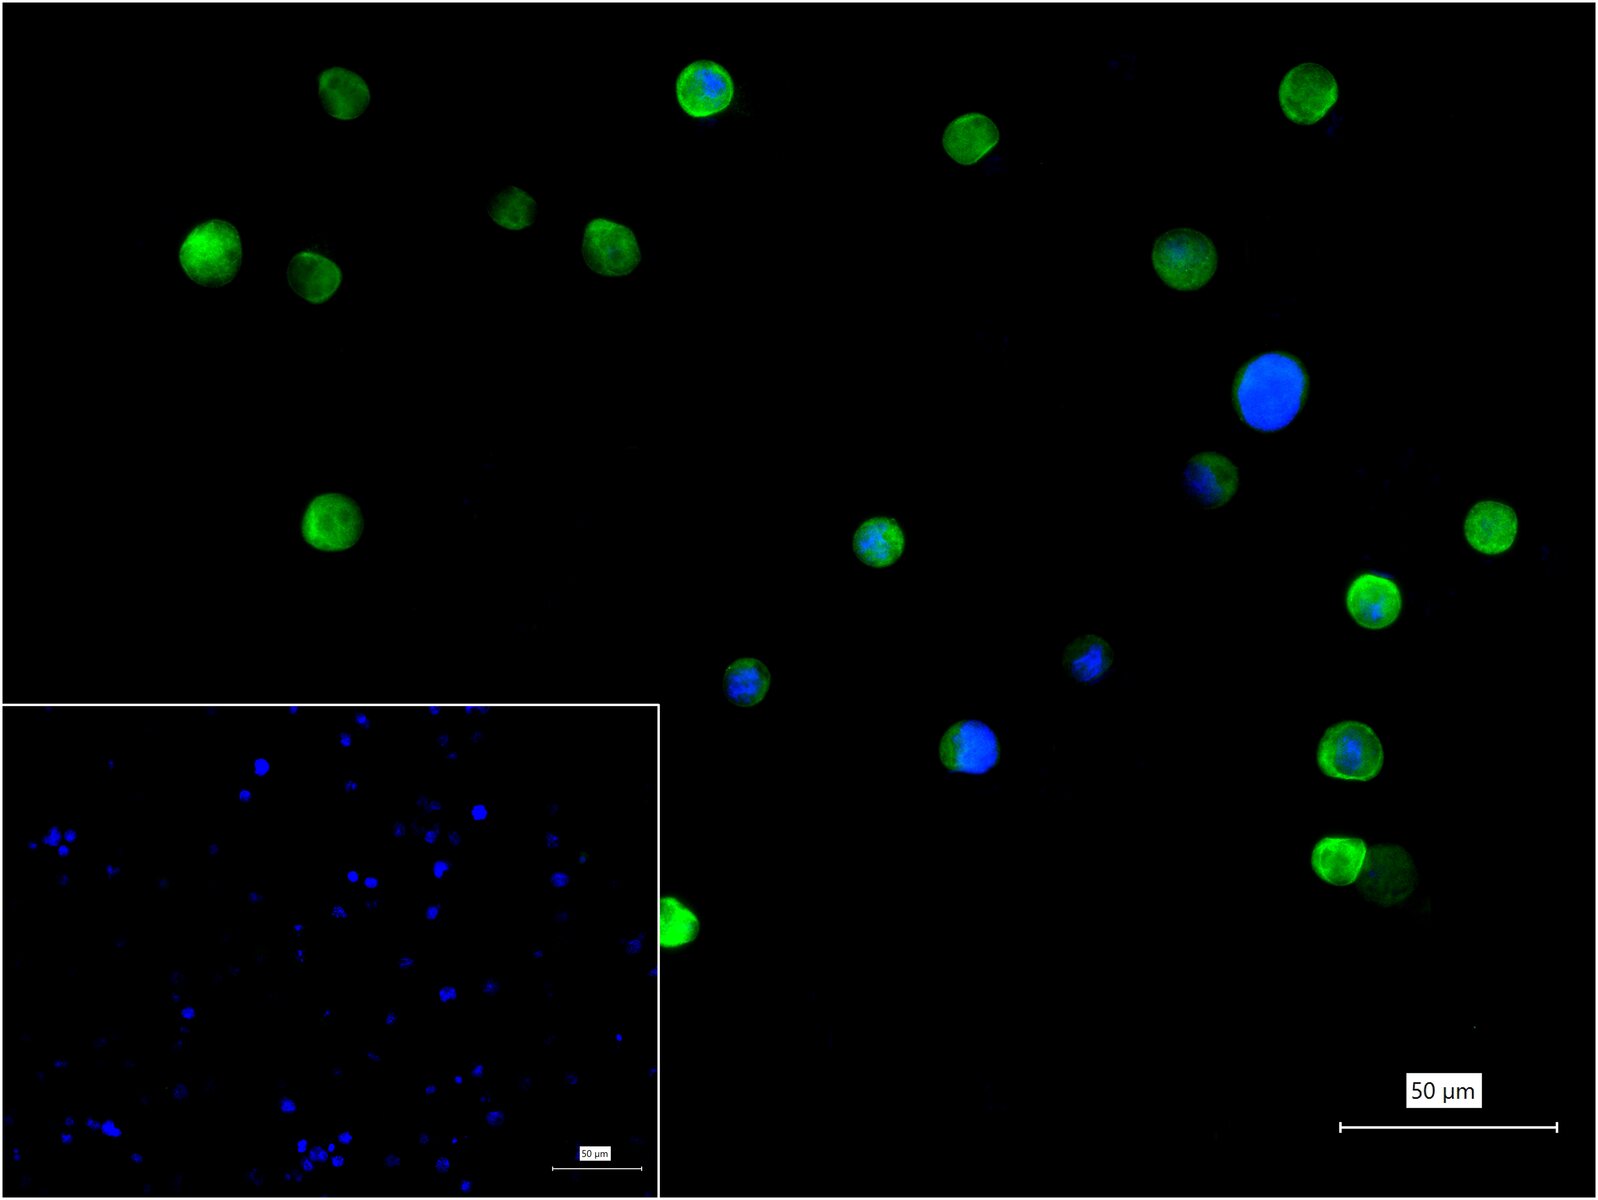

4% Paraformaldehyde-fixed K562 (H) cell; Triton X-100 at r.t. for 20 min; Antibody incubation with (Hsp90 alpha) monoclonal Antibody, unconjugated (bsm-52353R) 1:100, 90 min at 37°C; followed by BF488 conjugated Goat Anti-Rabbit IgG antibody (green, bs-60295G-BF488) at 37°C for 90 min, DAPI (blue, C02-04002) was used to stain the cell nuclei. PBS instead of the primary antibody was used as the blank control.

4% Paraformaldehyde-fixed Jurkat (H) cell; Triton X-100 at r.t. for 20 min; Antibody incubation with (Hsp90 alpha) monoclonal Antibody, unconjugated (bsm-52353R) 1:100, 90 min at 37°C; followed by BF488 conjugated Goat Anti-Rabbit IgG antibody (green, bs-60295G-BF488) at 37°C for 90 min, DAPI (blue, C02-04002) was used to stain the cell nuclei. PBS instead of the primary antibody was used as the blank control.